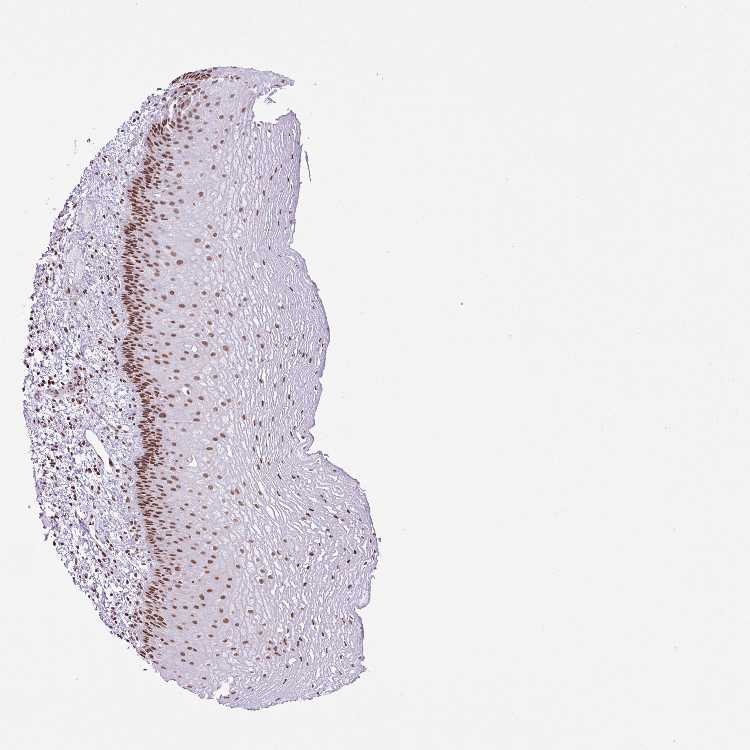

ESOPHAGUS - Antibody stainingi

Antibody staining in the annotated cell types in the current human tissue is reported as not detected, low, medium, or high, based on conventional immunohistochemistry profiling in selected tissues. This score is based on the combination of the staining intensity and fraction of stained cells.

Each image is clickable and will lead to virtual microscopy that enables deeper exploration of all samples and also displays staining intensity scores, fraction scores and subcellular localization as well as patient and tissue information for each sample.

Antibody HPA053883

Squamous epithelial cells High